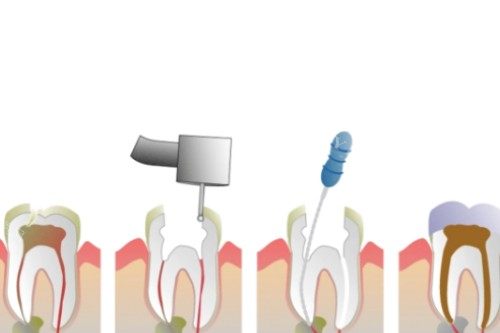

绍兴嵊州嵊新口腔根管治疗价格表

前牙根管治疗:300 元起

双尖牙根管治疗:500 元起

磨牙根管治疗:800 元起

单根管根管治疗:350 元起

双根管根管治疗:600 元起

三根管根管治疗:900 元起

四根管根管治疗:1200 元起

显微镜下根管治疗:1500 元起

一次性根管治疗:1000 元起

热牙胶根管治疗:1300 元起